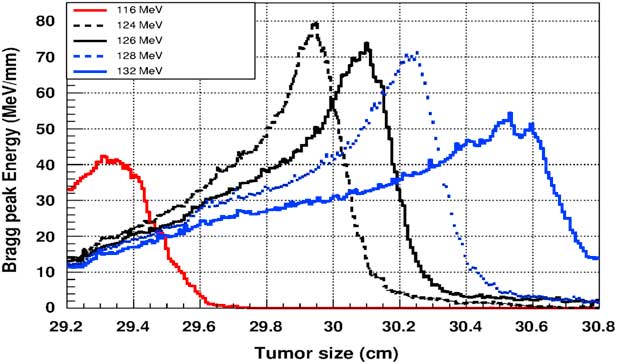

Figure 5 shows the plot of the deposited energy of a monoenergetic proton beam along the tumour size. As this figure shows, to surround completely a such tumour we should use a proton beam energy, ranging between 116 and 126 MeV. For this range energy, the Bragg peak energy is around 40 MeV and the half-value width for each Bragg peak is about 50% of the tumour size. The effect of adding gold in the tumour on the Bragg peak energy is shown in Figure 6. In this figure, we notice that the Bragg peak is localised in the tumour for the proton beam energy ranging between 116 and 130 MeV. The Bragg peak energy at the centre of the tumour is greater than without GNPs, in this case, with the presence of GNPs, the proton therapy is enhanced up to 75%, this is due to the concentration of GNPs at the centre of the tumour. Moreover, for high proton beam energy like 130 MeV, the width at half height of the Bragg peak is around of 75% of the tumour size. Comparing with previous results, the presence of GNPs in the tumour makes the width at half height of Bragg peak larger. This result shows that adding GNPs in tumours makes the proton therapy easier in clinical medicine and presents more benefit. Similarly in Figure 7, we plotted the deposited energy in the tumour with the presence of nanoplatinum materials. In this figure, the Bragg peak is localised in the tumour for the proton beam energy ranging between 116 and 132 MeV. Comparing with previous results, the width at half height of the Bragg peak is spread over 85% of the tumour. Moreover, the deposited energy at the centre in the tumour is almost double comparing with the same results in Figure 6. In the case of the use of silver NPs during this therapy, the plot of the deposited energy has the same shape as in the case of the use of GNPs (see Figure 8).

Figure 7 The deposited energy of a monoenergetic proton beam into the tumour with adding platinum nanoparticles. Notes: The proton beam energy is ranging between 116 and 132 MeV.